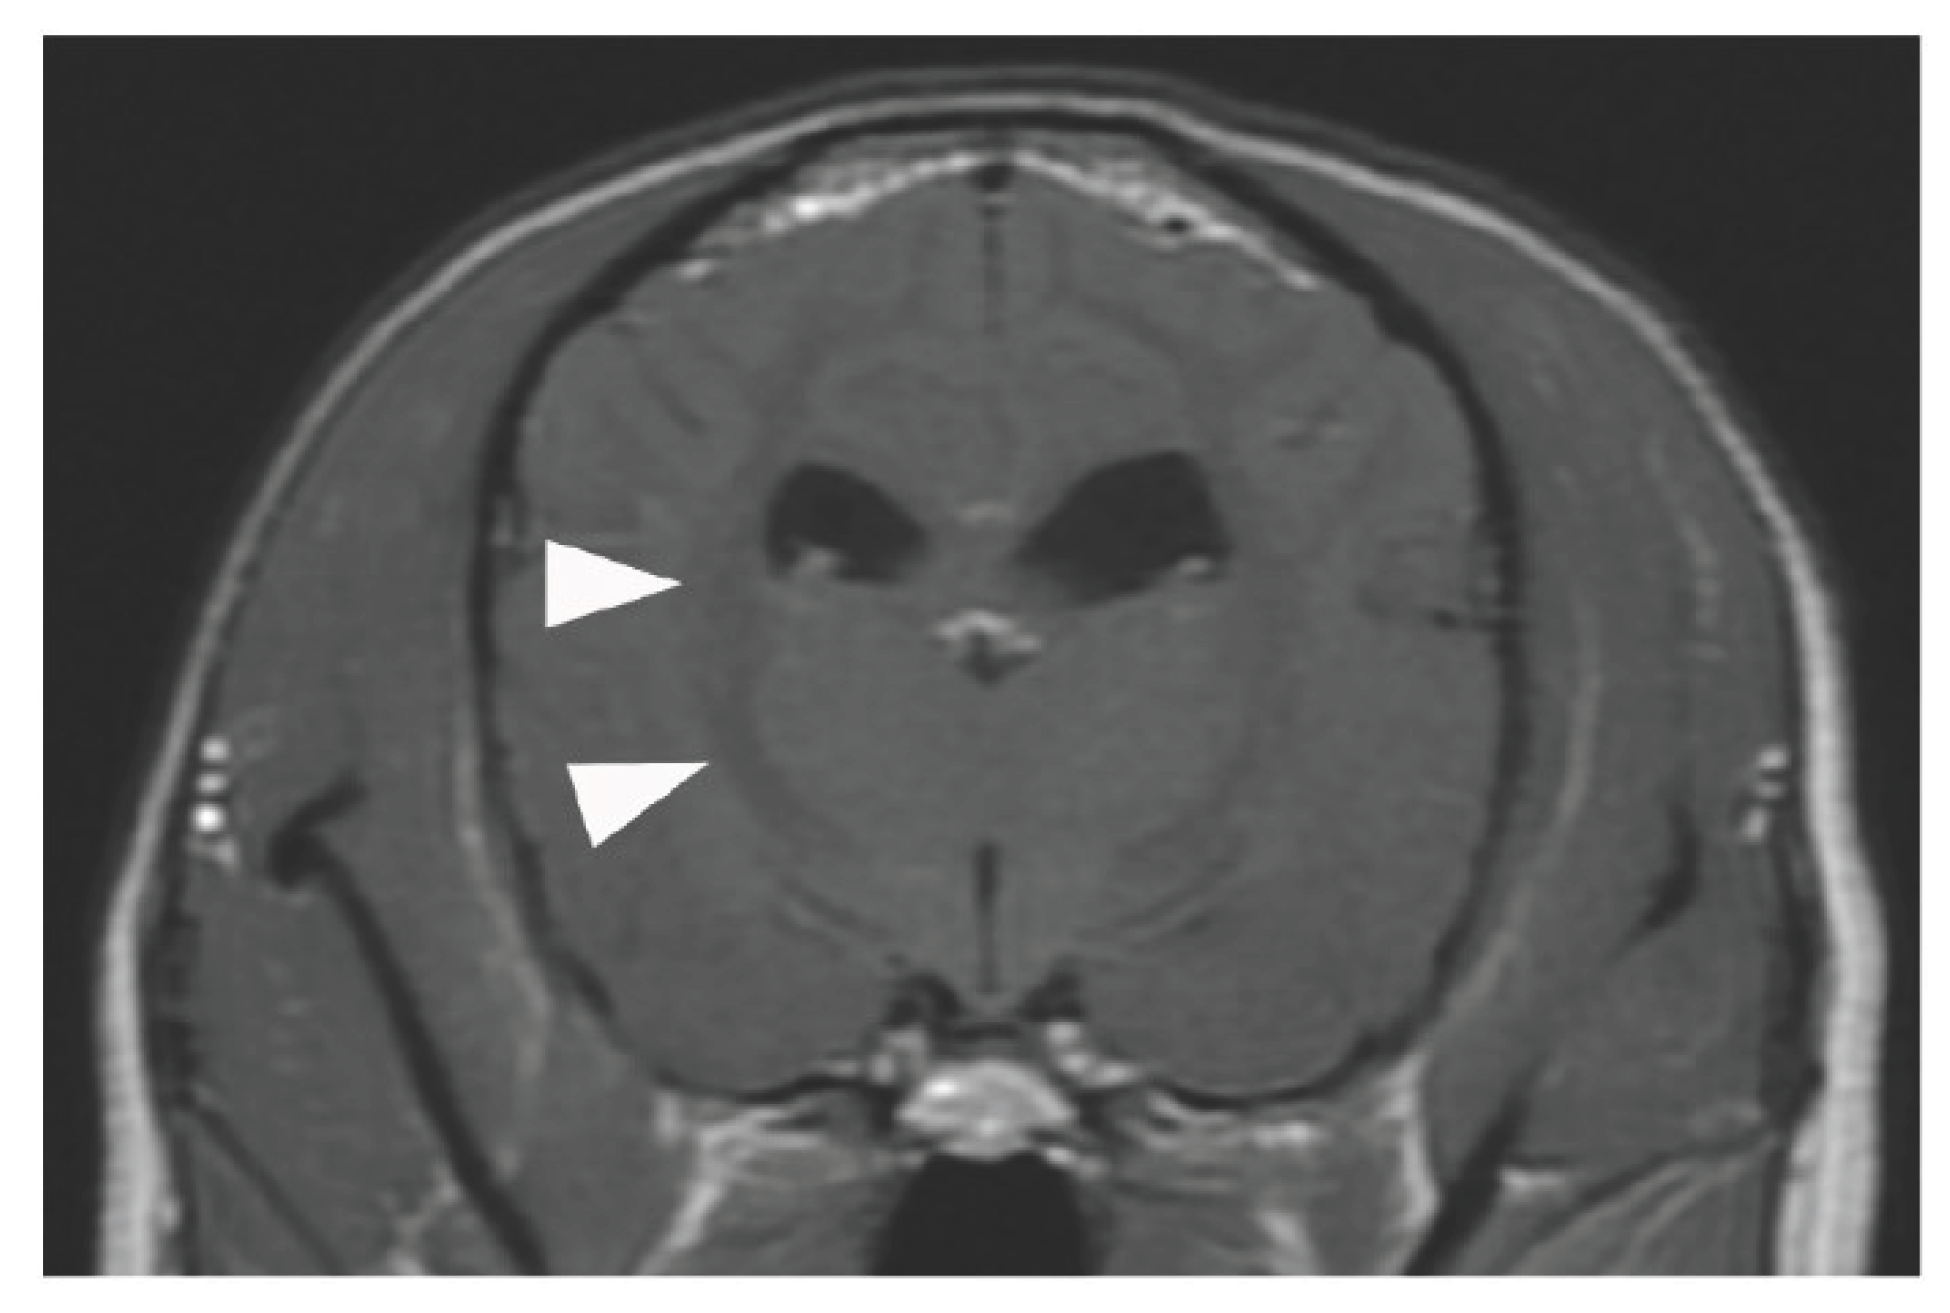

Echocardiography revealed low cardiac volume and tachycardia due to increased vascular permeability. Intravascular hypovolemia was suspected. Glycerine (10 mL/kg) and fresh frozen plasma (FFP) (15 mL/kg) were administered to prevent cerebral oedema. Glucose (1–2 g/kg/h), KCl (0.1–0.3 mEq/kg/h), and calcium gluconate hydrate (10–20 mg/kg/h) were administered as CRI, and the dose was controlled with blood examination each time. Dobutamine (0.5–3 µg/kg/min) and noradrenaline (0.02–0.1 µg/kg/min) were administered to control blood pressure. Seven hours after ECMO discontinuation, tachycardia improved, but the albumin level decreased (1.7 g/dL). Therefore, FFP was re-administered, which increased the albumin level to 2.8 g/dL. Glycerine was also administered to prevent cerebral oedema caused by continued low urine output. The patient stabilized, but 20 h after ECMO discontinuation, mild hypotension and decreased albumin (2.1 g/dL) were observed; hence, FFP was administered again. Glycerine was administered every 12 h. The urine output increased to 15–30 mL/kg/h 24 h after ECMO discontinuation. Stick urinalysis, performed because of polyuria, revealed an occult blood reaction (2+) and negative results for glucose, ketones, and bilirubin. Sodium phosphate correction was performed to treat the electrolyte abnormalities caused by polyuria. The patient was managed under anaesthesia with sevoflurane 1.5–2.0 minimum alveolar concentration and rocuronium bromide 0.4 mg/kg/h to prevent brain damage due to prolonged hypoxia and high carbon dioxide levels. Since the respiratory status was good (SpO2, 100%; ETCO2, 54 mmHg; pH, 7.305; pCO2, 51.0 mmHg; pO2, 187 mmHg; P/F, 311) under a ventilator setting of RR of 32/min, PEEP of 6 cmH2O, PIP of 20 cmH2O, and FiO2 of 0.6, the patient was weaned off rocuronium bromide (constant rate infusion) and switched to spontaneous breathing with pressure support mode (RR, 20/min; PEEP, 6 cmH2O; pressure support, 15 cmH2O; FiO2, 0.4). At 26 h after ECMO discontinuation, the results of blood gas analysis, blood biochemistry tests, and complete blood count were good (SpO2, 100%; ETCO2, 37 mmHg; pH, 7.338; pCO2, 47 mmHg; pO2, 126 mmHg; P/F, 315; haematocrit, 39%; platelet, 11.5×104/μL). The eyelid reflex and swallowing response were promptly observed, and the patient was extubated 28 h after ECMO discontinuation. After recovery from anaesthesia, the level of modified Glasgow Coma Scale (MGCS) was 16, and the dog was able to turn around and change its position independently when called by its name. The patient was also able to drink water and consume liquid foods. However, 6 h after extubation, head tremors were observed (Video S2). Temporary improvement was observed after intravenous administration of diazepam (0.5 mg/kg). However, as the tremors continued, continuous diazepam was administered, and hyperthermia, panting, and involuntary movements appeared, and the MGCS dropped to 10. Sedation was reinforced, but repeated panting and respiratory arrest occurred; therefore, the patient was intubated again 18 h after extubation, and respiratory control was performed. Because of the pronounced neurological symptoms, we considered the high body temperature and panting to be due to brain damage and the repeated administration of glycerine and anticonvulsants. The patient was extubated after the respiratory arrest resolved, but sedation was continued. However, the high body temperature and involuntary movements persisted. On day 6, the patient’s hyperthermia and involuntary movements improved, and all medications used for sedation management were discontinued. However, the patient’s consciousness did not improve, although mild eyelid reflex and swallowing response were observed. Cranial magnetic resonance imaging (MRI) and electroencephalography (EEG) were performed to assess the brain damage. The white matter showed hyposignal on T1-weighted and post-contrast T1-weighted MRI (Figure 3).

No haemorrhage, infarction, cerebral oedema, or cerebral herniation was observed. EEG examination showed no apparent abnormal waveforms. The eyelid reflex and swallowing response progressively weakened, the MGCS was reduced to 3, and the patient died on day 8 from respiratory arrest without regaining consciousness. The owner did not request further resuscitation.

According to the Extracorporeal Life Support Organization guidelines, ECMO is indicated for bronchoalveolar lavage in cases of severe inhalation injury. In this case, the patient developed upper airway obstruction secondary to barium aspiration, constituting a severe inhalation injury that met the criteria for extensive bronchoalveolar lavage, as defined by [9], the International Organization for Human ECMO. Given that the patient was young (3 years), exhibited good energy and appetite, and had no underlying chronic diseases, a full recovery could allow it to lead a normal life. Therefore, ECMO was not contraindicated and was indicated for prompt introduction. However, due to the owner’s reluctance and our inexperience in using the modality, a long duration elapsed between the presentation with respiratory failure and the introduction of ECMO, resulting in prolonged hypoxia. Oxygenation was maintained by ECMO, which enabled tracheobronchial lavage with complete airway occlusion. Following the lavage procedure performed under ECMO support, barium was completely removed and the respiratory status improved drastically, the dog was allowed to drink water after extubation. MRI demonstrated no brain herniation or ECMO-related complications commonly reported in human medicine, such as cerebral hemorrhage or stroke [4,10]. Therefore, the patient might have survived with no hypoxia-related brain damage [11] if early intervention had been performed. Currently, no indication criteria exist for the use of ECMO in veterinary medicine. However, human studies have reported that early initiation of ECMO improves survival in cases of acute respiratory distress syndrome [12], pulmonary hypertension [13], coronavirus disease 2019 [14], and cardiogenic shock [15,16,17]. Based on these findings, we strongly believe that the same principle applies in the veterinary field. If ECMO is associated with a high probability of survival, it should be applied proactively and without delay.

Figure 3. Contrast-enhanced T1-weighted magnetic resonance image of the brain. No common ECMO-related complications suggestive of cerebral herniation due to thrombus, haemorrhage, or oedema were observed. However, the white matter showed an overall low signal (arrowhead), suspected as brain damage caused by the prolonged hypoxia before ECMO was introduced. ECMO, extracorporeal membrane oxygenation; HR, heart rate; BP, blood pressure; FFP, fresh frozen plasma.